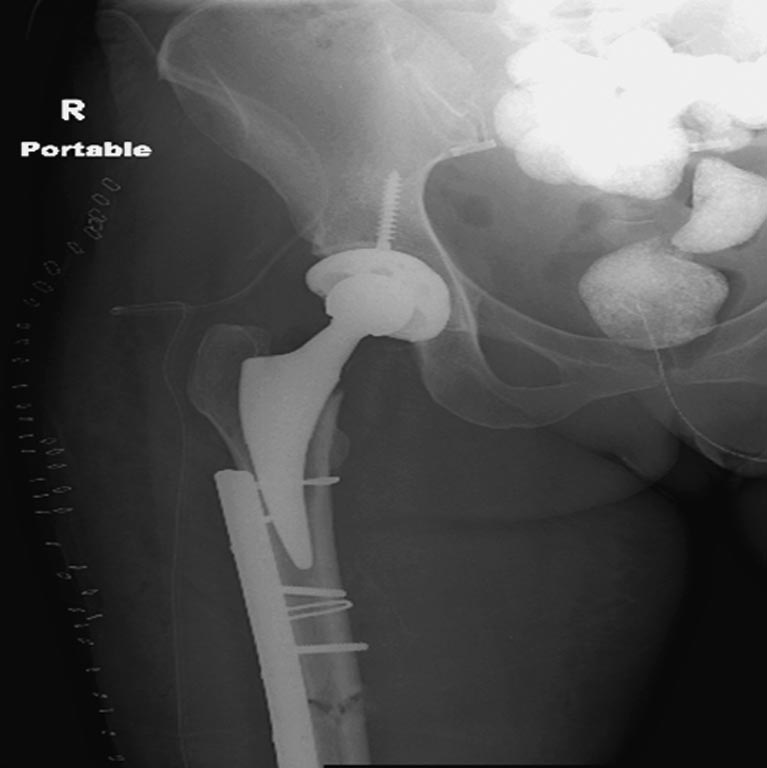

На 25 день с момента травмы операция на Jackson table с боковым обширным доступом. Удаление стержней с местной обработкой. В тазобедренном суставе удаление головки, на дне вертлужной впадины полная отслойка хряща. Вертлужный компонент с одним винтом и короткая ножка - Fitmore press fit stem. На второй день однократно доза радиации для профилактики гетеретопической оссификации. Послеоперационный период без температуры. Выписана. Нагрузку разрешили на левой стороне, а полная в 3 мес. Здесь снимки при амбулаторном наблюдении: послеоперационно, 2 мес, 3 мес и 6 мес. Нагрузка полная, отсутствует хромота, и нет жалоб.